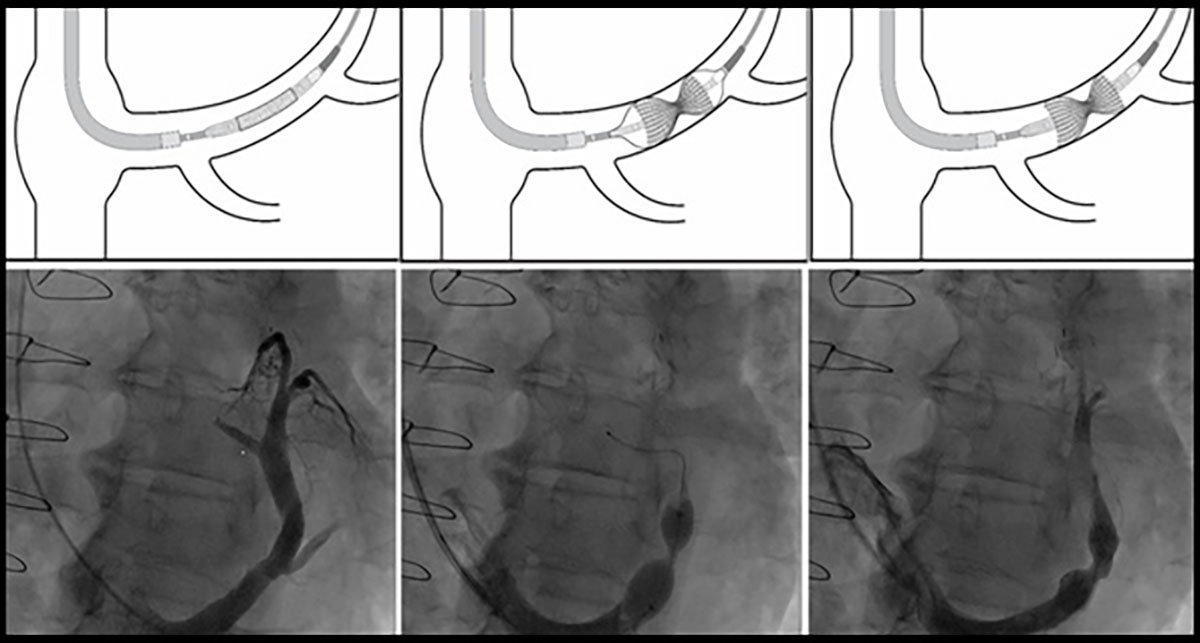

🚨 Just out in @JACCJournals: Our meta-analysis on the safety, efficacy & effectiveness of the Coronary Sinus Reducer (#CSR) for #RefractoryAngina 🫀 📄 Open access: https://t.co/xa7Z7lW0AF @rallamee @CardioKarsh @MikeFoley89 #Cardiology #InterventionalCardiology

Coronary sinus reducer implantation may be safe & feasible, w/ promising antianginal efficacy in patients w/ refractory angina, according to a meta-analysis published in #JACCINT. However, larger trials are needed to assess efficacy. Read more: https://t.co/6jVtZIAJ1s

Hot off the press!! 🔥 🗞️ Our editorial comment about the Coronary Sinus Reducer device with @DLBHATTMD at @JACCJournals. A promising device for our patients with refractory angina 💊@SinaiCards @MountSinaiHeart https://t.co/GoRoTiffWh